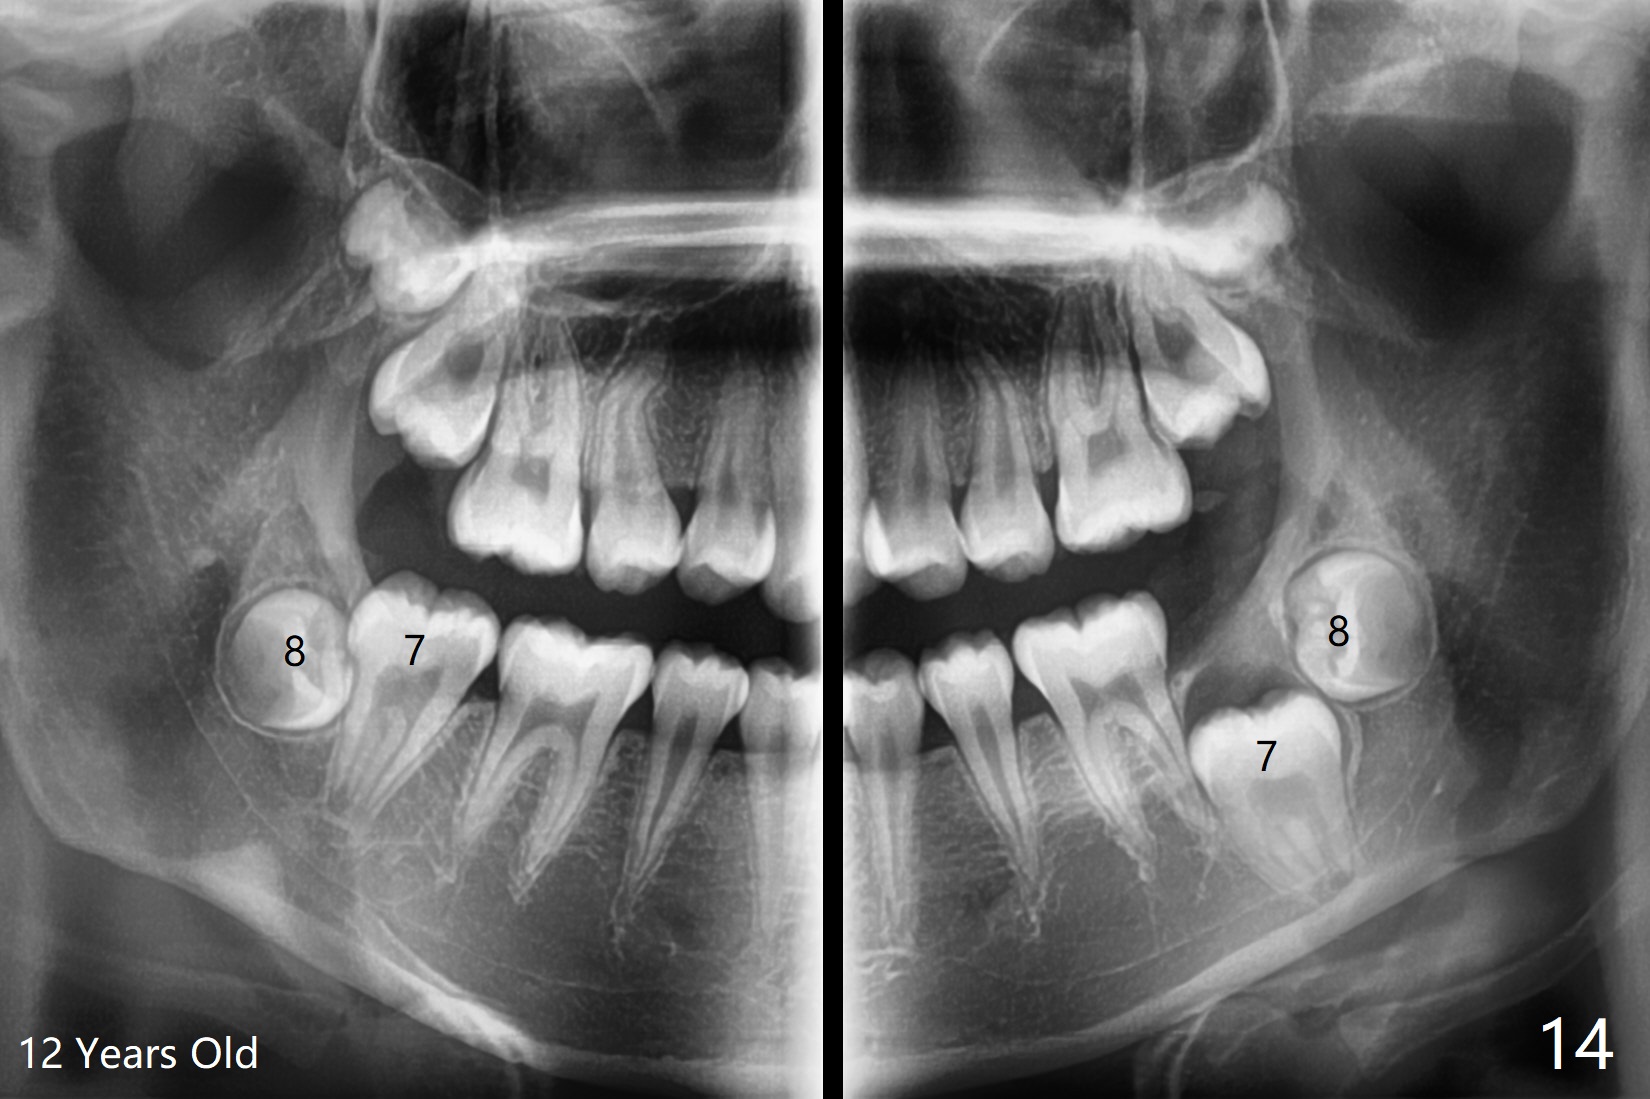

A 12-year-old woman has Class I facial profile (Fig.1-4,12,13) and apparently Class II Division I malocclusion (Fig.6-11). Start Class II retraction as early as possible to take advantage of the upper and lower posterior diastemata (Fig.9,11 (in fact there is no diastema)). LL7 impaction is noted immediately prebanding (Fig.14). Surgical access is pending.